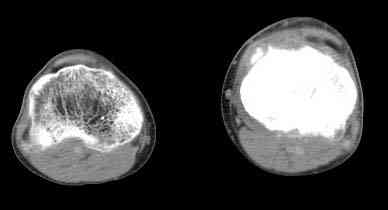

важаемые коллеги! Поступил больной 22 лет. Болен с января 2006 - появились боли в области верхнейтрети голени. При первичном осмотре в поликлинике был заподозрен первично-хронический остеомиелит - осмотрен гнойным хирургом - произведена биосия . Заключение - хондросаркома. Осмотрен онкологом - с учетом характера опухоли - химиотерапия, лучевое лечение не показано. Предложена либо ампутация, либо решение вопроса о возможности выполнения органосохраняющей операции. При обращении к нам произведена сцинтиграфия скелета - зоны гиперфиксации РФП: верхняя треть голени- 960%, нижняя треть бедра - 380%, Дистальный метафиз голени и затылочная область - 140%. В легких - метастазов нет. Произведена КТ (картинки в приложении). Учитывая абсолютную нестыковку рентгенологических и морфологических данных повторно биопсия. Выявлено, что первичная биопсия выполнялась из поверхностной параоссальной зоны - там локализованы хрящеподобные массы, далее очень плотная кость без хрящевых участков - биоптат взят фрезой с большим трудом. Морфологического заключения пока нет. Хотелось бы узнать Ваши варианты диагноза и соответственно тактику.